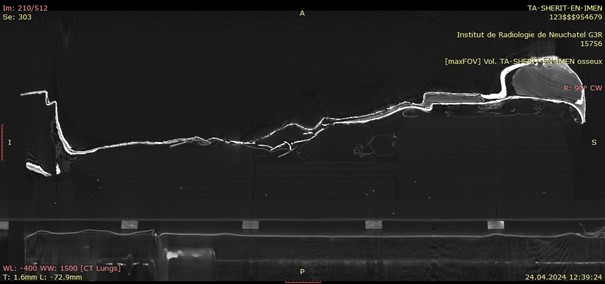

April 2021 | Computed tomography of the mummy

The mummy of Ta-sherit-en-Imen was scanned on April 6 2021 by the team of Dr. Frank Rühli and Patrick Eppenberger of the Swiss Mummy Project, Institute of Evolutionary Medicine of the University of Zurich (IEM). 3,938 sectional axial images with a slice interval of 0.4 mm and a slice thickness of 0.6 mm were reconstructed from the acquired raw data and used to evaluate the findings. The interpretation of the mummification process was completed by Dr. Jonathan Elias from the Akhmim Mummy Studies Consortium (AMSC). A sample of thigh bone was removed, and C-14 dated by Dr. Irka Hajdas from the Laboratory of Ion Beam Physics at the ETH Zurich.

Based on the level of ossification of the cranial sutures, Ta-sherit-en-Imen died as a young adult aged between 27 and 35 years somewhere around 824-780 BC (calibrated C-14 date of bone material). The cause of death was possibly two blows to the frontal-parietal cranium that left two large lesions of the outer compacta, as well as three fracture lines. Since there is no evidence of bone remodeling, she must have died shortly after the incident. The localization of the trauma indicates a foreign impact rather than an accidental lesion.

The mummification process was cursory and done without eviscerating internal organs, which is not unusual for the Third Intermediate Period. This led to subsequent disintegration of the soft tissues and the misalignment of the neck and thoracic skeleton (fig. 2). There are no signs for excerebration of the brain and the nasal cells remain intact. The left and right hemispheres of the brain have split at the corpus callosum and fallen on their respective sides (fig. 3).

The individually wrapped arms are arranged angled downwards to the thigh crease with the hands arranged in a relaxed position and nearly touching one another. Three textile packages have been secured to the front of the neck and are held in place by resin coated textile bandages. Such neck packages are frequently found on mummies from that period and seem to be part of the original mummification process. Further textile packages are located on the collapsed left thoracic area as well as in between the legs. Resin was applied onto the bandages twice during the wrapping procedure and can be seen as denser white lines on the scans. The most outer resin coated textile layer can be seen in the middle section of the mummy where outer wrappings were subsequently stripped away. Its hard resinous matter thankfully prevented the complete unwrapping of the mummy.